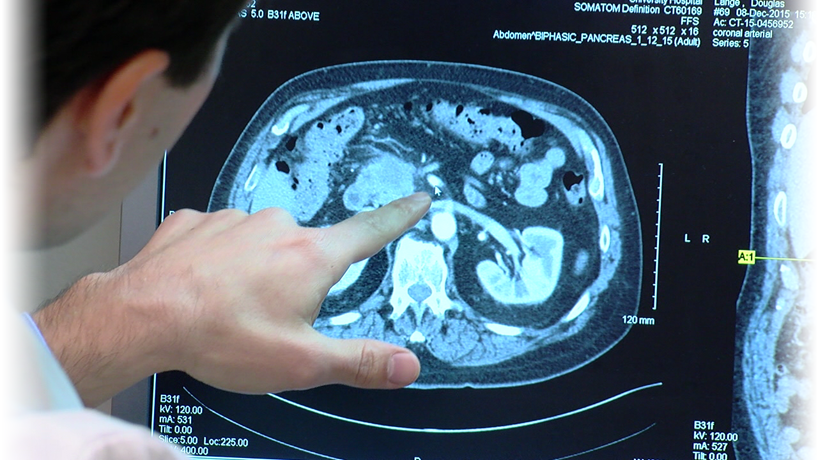

Методы динамического контрастирования печени на МРТ

Раздел: Снимки-подсказки